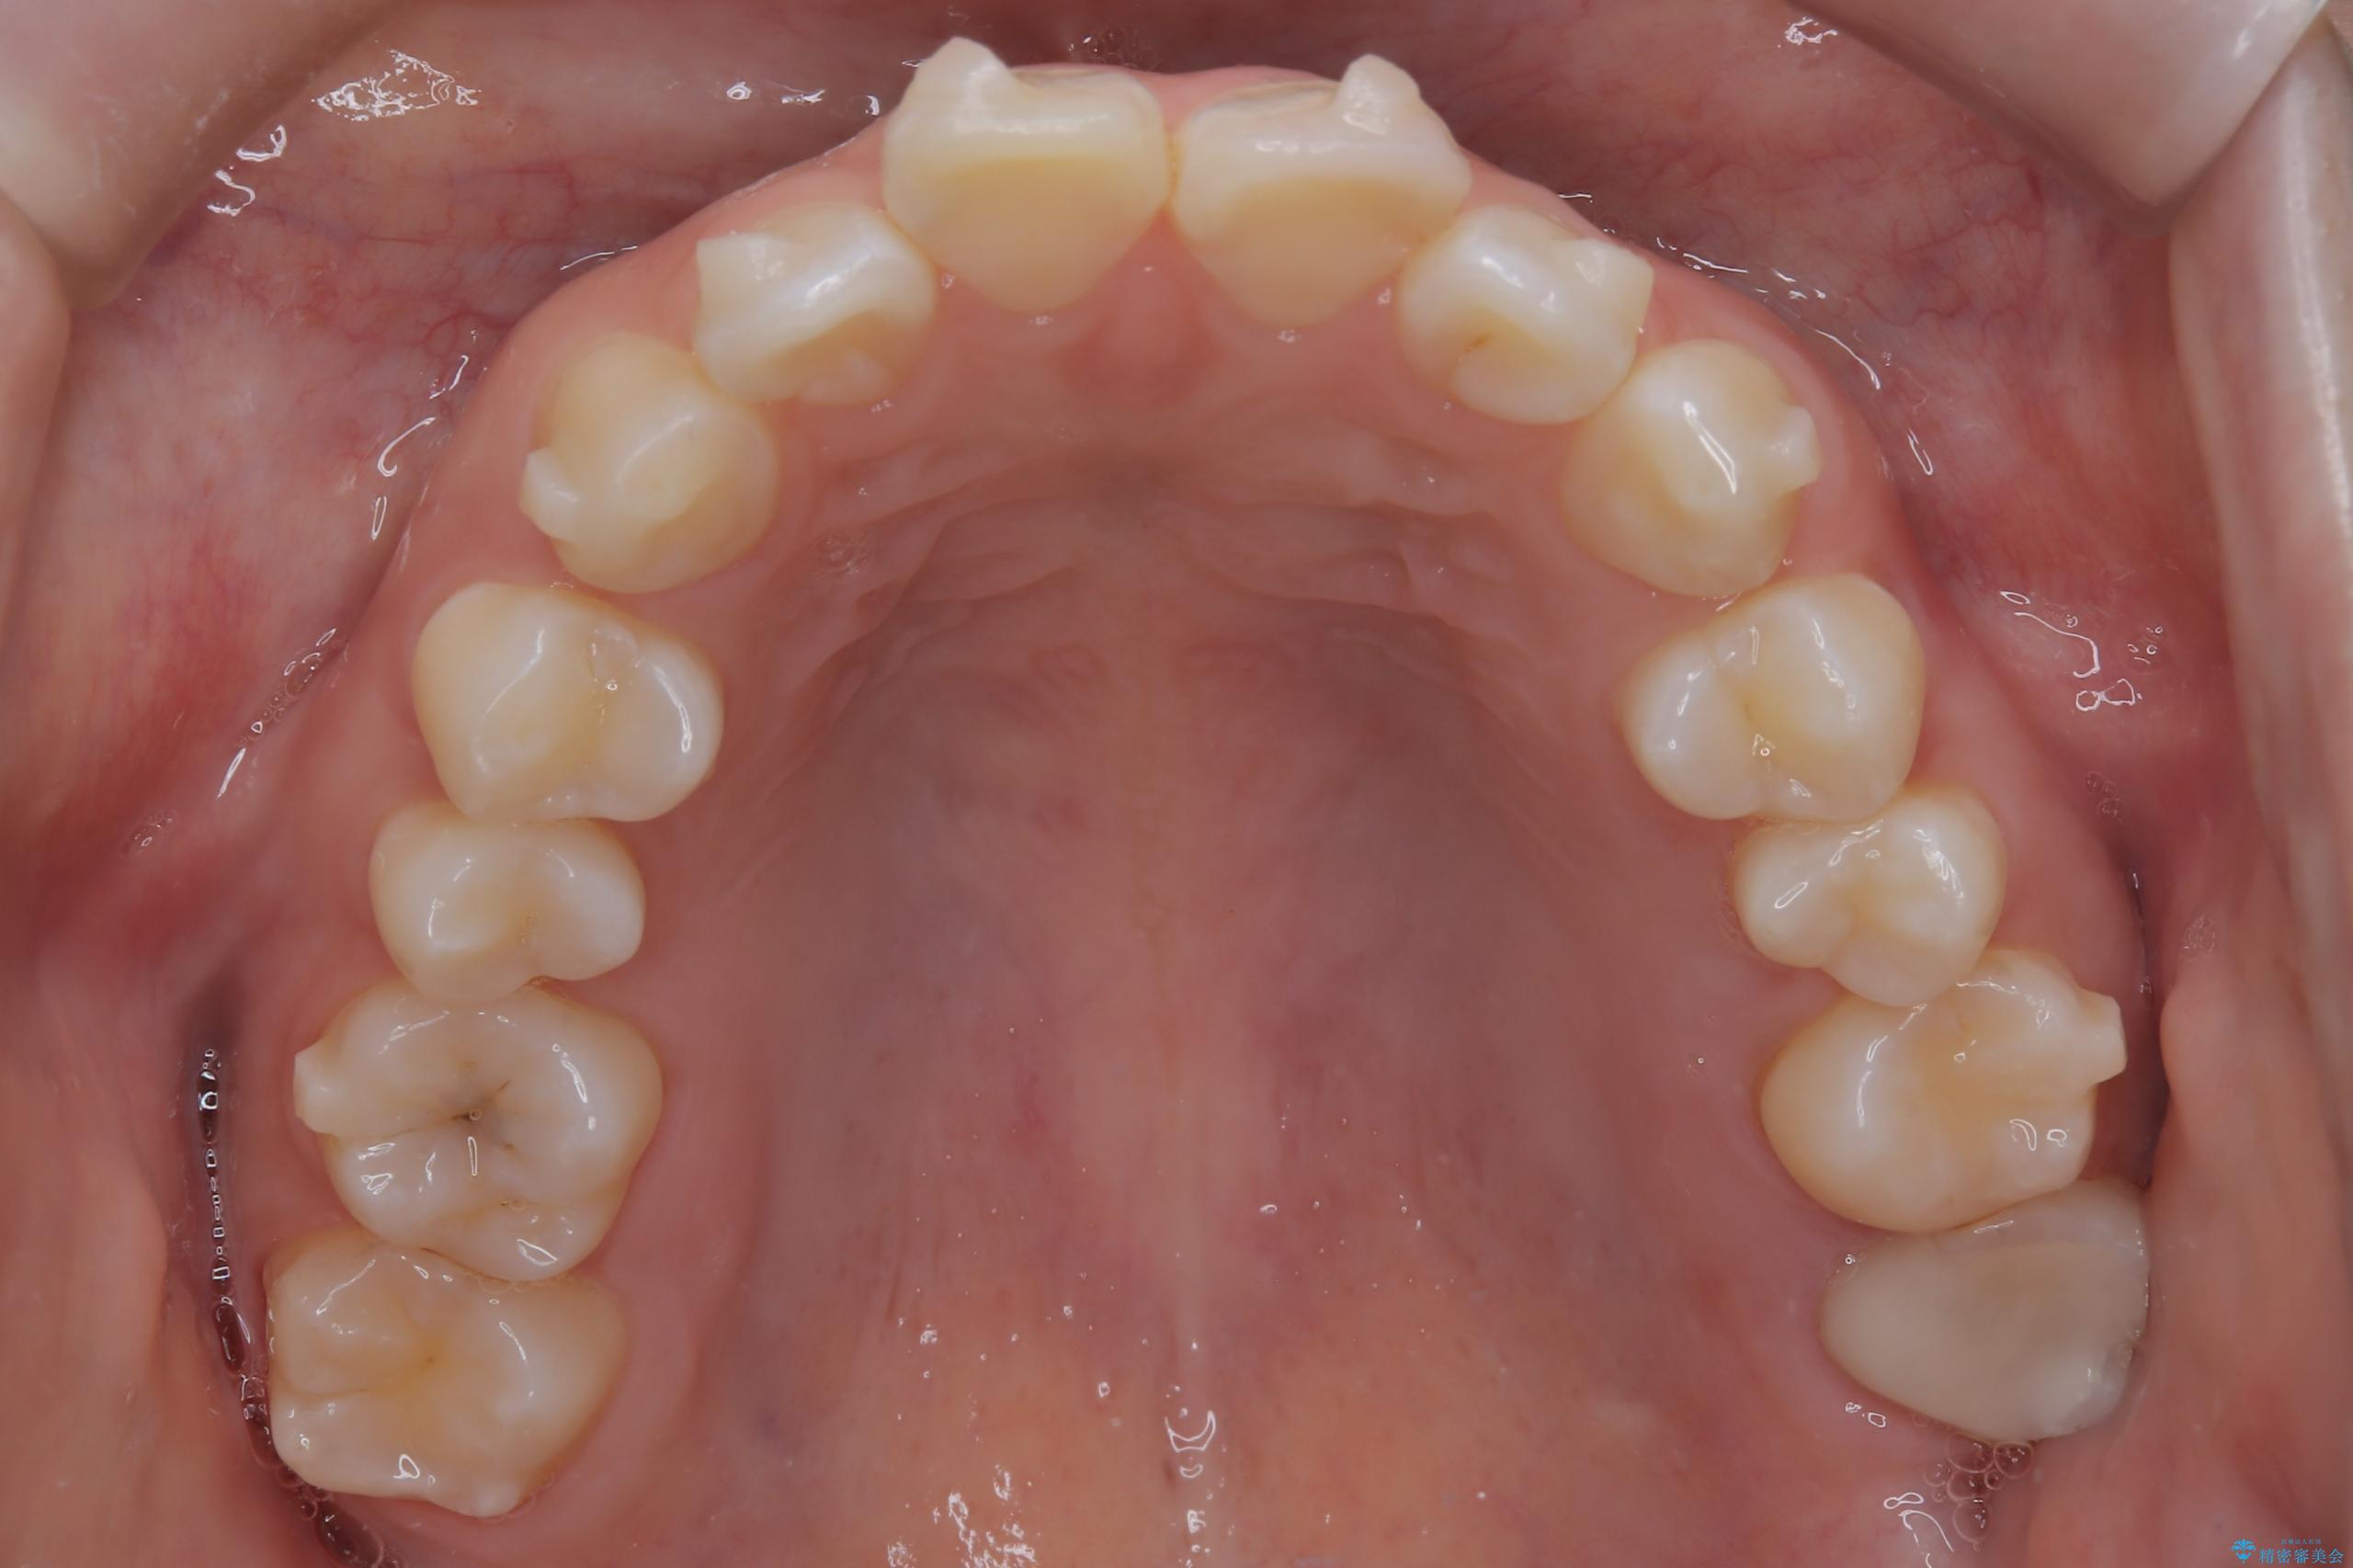

- 前歯のデコボコ(叢生)を気にされてご来院されました。精密な検査の結果、歯が並ぶスペースが不足していることが判明。患者様のご希望から、透明で目立ちにくいインビザライン(マウスピース矯正)による治療計画を立案しました。抜歯を避け、奥歯全体を奥へ動かす遠心移動という方法でスペースを確保し、前歯の叢生を解消することを目指します。

今回の矯正治療では、透明なマウスピース型の装置インビザラインを使用しました。この装置は取り外し可能で、日常生活で目立ちません。治療は、緻密に計算された計画に基づき、段階的に作製されたマウスピースを交換していくことで、奥歯から順に全体を後方へ移動させる遠心移動を実施。これにより、前歯を並べるための十分なスペースが確保され、デコボコが解消されました。抜歯することなく、機能的にも審美的にも整った美しい歯並びを獲得していただけました。